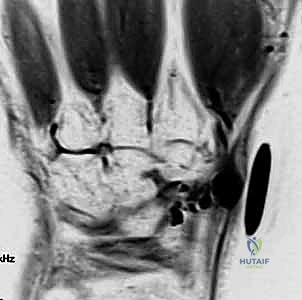

- التصوير بالموجات فوق الصوتية (Ultrasound): طريقة سريعة وفعالة لتأكيد التشخيص وتحديد ما إذا كان الورم يحيط بالأوعية الدموية.

- الرنين المغناطيسي (MRI): هو المعيار الذهبي الذي يطلبه الدكتور هطيف في الحالات المعقدة أو الأورام العميقة غير الظاهرة، لتخطيط الجراحة بدقة متناهية ومعرفة ارتباط الورم بالهياكل الحيوية.

لفهم خطورة وأهمية جراحات أورام اليد، يجب أن نلقي نظرة على التشريح المذهل لهذه المنطقة. يتكون المعصم من ثماني عظام صغيرة (عظام الرسغ) مرتبة في صفين، وترتبط ببعضها بأربطة قوية جداً. يمر عبر هذا المعصم الضيق (نفق الرسغ) أوتار العضلات القابضة بالإضافة إلى العصب المتوسط (Median Nerve).

هو الورم الأكثر شيوعاً على الإطلاق في اليد والمعصم. يظهر ككتلة ملساء تحت الجلد، وغالباً ما يكون متصلاً بمفصل المعصم أو بغمد أحد الأوتار. يحتوي هذا الكيس على سائل هلامي زلالي لزج يشبه سائل المفاصل ولكنه أكثر كثافة. يمتلك الكيس "جذراً" أو "عنقاً" يربطه بالمفصل، وإذا لم يتم استئصال هذا الجذر بالكامل أثناء الجراحة، فإن نسبة عودة الكيس تكون مرتفعة جداً.